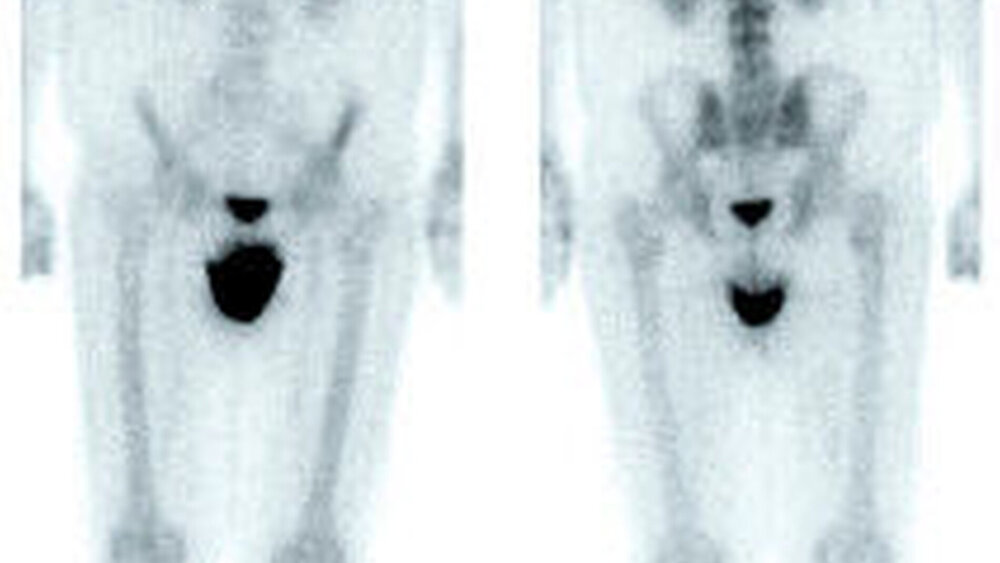

Dreiphasen-Szintigrafie: Die planare Dreiphasen-Szintigrafie mit 99m Tc-markierten Bisphosphonaten ist ein nuklearmedizinisches Standardverfahren in der Diagnose der Kieferosteomyelitis/-nekrose. Sie zeigt die Lokalisation von vermehrtem Knochenumbau (Osteoblastenaktivität) mit hoher Sensitivität an (Abbildung 6). Das Verfahren ist jedoch nicht spezifisch und hat nur eine begrenzte Ortsauflösung [Stockmann et al., 2010].

SPECT(single photon emission computed tomography)-Technik: Die diagnostische Akkuratesse der Szintigrafie kann durch Verwendung der SPECT gesteigert werden (Abbildung 2) [Dore et al., 2009]. Hier werden anders als in der Szintigrafie (in der Aufnahmen aus ventraler und dorsaler Projektion aufgenommen werden) mehrere Aufnahmen aus unterschiedlichen Winkeln akquiriert, aus denen ein dreidimensionales Bild errechnet wird. Dies verbessert die Detektion und die örtliche Zuordnung von fokal vermehrten Traceranreicherungen im Vergleich zu Szintigrafie oder CT allein [Bolouri et al., 2013].